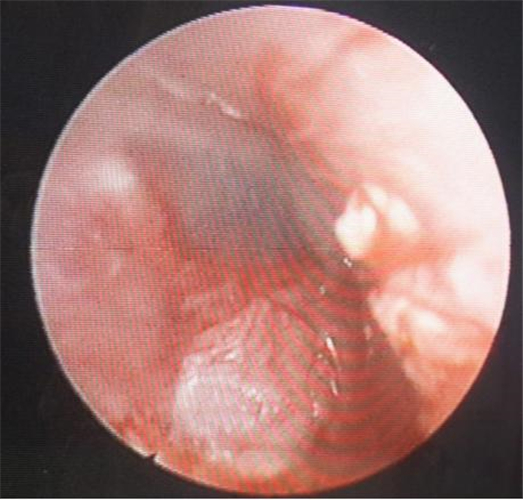

自愈的鼓膜穿孔